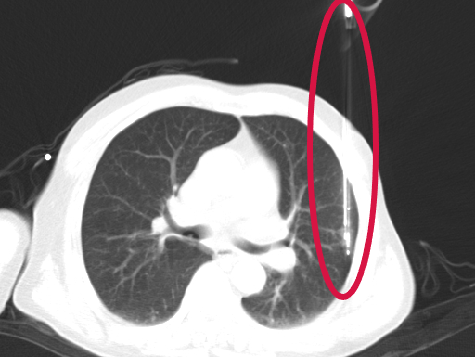

活檢槍置入

▲患者因體檢發(fā)現(xiàn)左肺上葉舌段結(jié)節(jié),考慮周圍型肺癌可能。因高齡、肺氣腫無法手術(shù),遂來院接受肺結(jié)節(jié)冷凍消融治療,術(shù)后病理為肺癌,定期隨訪提示腫瘤逐漸縮小。